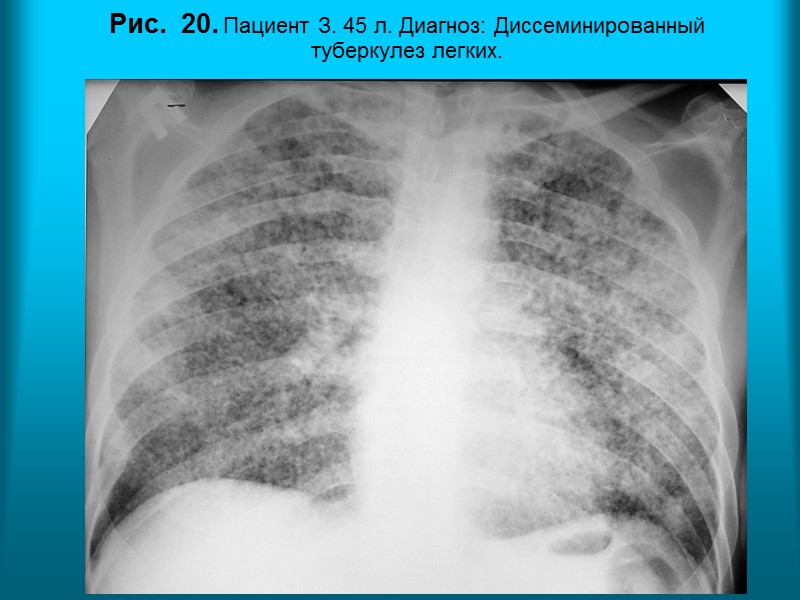

Н.С. Воротынцева. С.С. Гольев Рентгенопульмонология Рис. 20. Пациент З. 45 л. Диагноз: Диссеминированный туберкулез легких.